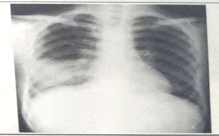

試題1:男性,26歲,受涼后寒顫高熱,咳嗽,咳鐵銹色痰5天(2分)

A.肺癌

B.氣胸

C.正常胸片

D.肺炎

E.胸腔積液

答案:D